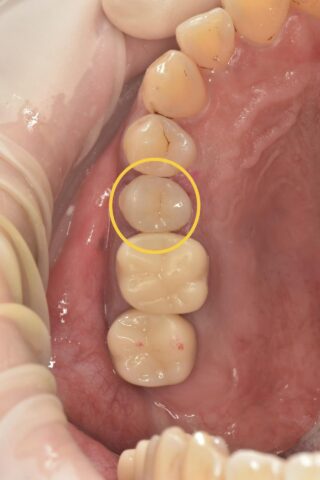

今回の部位は右上5番です

元々は金属の詰め物が入っていました。

黄色く囲んでいるのは1回目の治療で詰められたセメントです。神経付近まで削った際に使われるもので、第二象牙質の生成を促進する効果があります。

こちらが治療後の写真です

この補綴はオンレーといって鍋の蓋のような構造をしています。噛む面を全て覆っているため被せ物に近い強度が得られます。また、被せ物に比べて歯の切削量が少なく済むため、当院では多く用いられています。